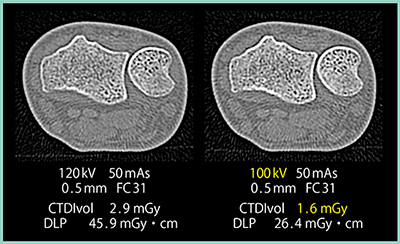

なお,エリアファインダ使用時はスキャノ画像からAuto Exposure Control(AEC:自動露出機構)が使用できないため事前に条件設定をする必要があるほか,GENESISでは実効エネルギーが高いため従来より線質が硬くなっているという実感がある。そこで,GENESISでは管電圧を100kVに設定した方がよいのではないかと考え,実際に120kVと100kVの画像を比較した(図3)。その結果,100kVの方が皮質骨や海綿骨のコントラストが明瞭であったことから,当院では現在,手関節の撮影条件を100kV,50mAsとしており,結果として被ばく低減にもつながっている。

図3 GENESISにおける管電圧の違いによる画質への影響